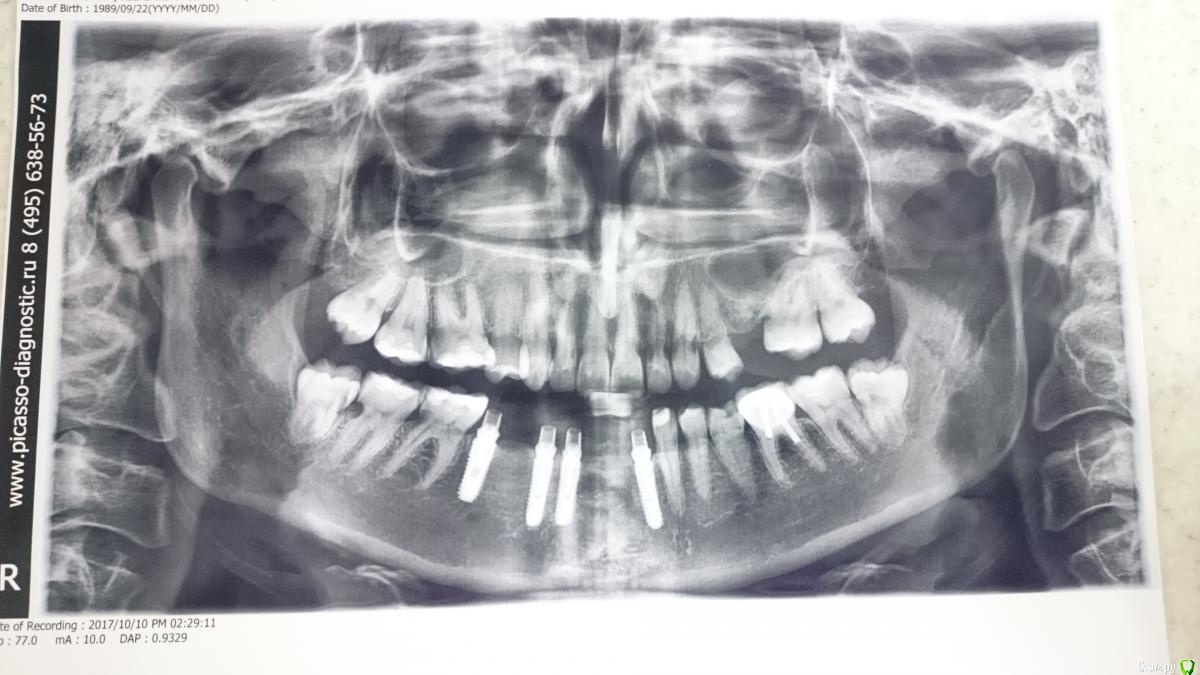

lightella Опубликовано 6 февраля, 2018 Поделиться Опубликовано 6 февраля, 2018 Здравствуйте, коллеги. В клинику обратилась пациентка 1989г.р.Орто 2015г.А это уже 2017Девушка в отчаянии, мы тоже че то приуныли.Кто может - пожалуйста, поделитесь опытом или информацией. Ссылка на комментарий

lightella Опубликовано 8 февраля, 2018 Автор Поделиться Опубликовано 8 февраля, 2018 (изменено) воздержусь до ответовОтвечаю. Девушка не спортсменка. Соматически здорова (обследовалась вдоль и поперек именно из за данной проблемы). Единственное, к чему можно придраться - один из анализов на гормоны ЩЖ оказался на десятую долю ниже нижней границы. На этом основании выставлен гипотиреоз (вот не знаю, насколько это правомерно, учитывая, что всего один показатель нарушен). Систематический прием каких либо препаратов отрицает.Гигиена приемлемая, не идеал, но выше среднего, скажем так. Множественого кариеса нет. Насколько я знаю, пациентка смирилась с тем, что лишится зубов. Знать бы еще, какие подводные камни могут быть при имплантации в подобных случаях. Изменено 8 февраля, 2018 пользователем lightella Ссылка на комментарий

lightella Опубликовано 8 февраля, 2018 Автор Поделиться Опубликовано 8 февраля, 2018 Резорбция не кариес. Тут нет такой зависимости от гигиены .Я так понимаю, доктор (dentikl) имеет в виду, что резорбцию спровоцировала агрессивная профгигиена. Не берусь утверждать, но мне это кажется маловероятным.тогда речь Может Идти о сочетании неудачной гигиены и удачной последней панорамы.Поясните, пожалуйста. Особенно насчет панорамы - в чем ее удача? И еще, по поводу связи со спортом интересно. Как у нее было изначально с гигиеной?Как это оценить ретроспективно? Как было с финансами в 15 году?Не знаю. И в каком контексте об этом спросить пациентку - тоже не знаю. По поводу чего в 15 делали панорамуВозникли жалобы, панорама была для предварительной диагностики. почему не вмешивались тогда? Вполне себе вмешивались, депульпировали и даже протезировали. В нашу клинику она попала только сейчас, даже импланты не наши.Ваш врачебный опыт и специализация?Терапия. В каких величинах измеряется опыт я не знаю. 10 лет +/- декрет. Ссылка на комментарий

lightella Опубликовано 23 февраля, 2018 Автор Поделиться Опубликовано 23 февраля, 2018 Просто предположение, но как вариант. Цервикальная резорбция этиологически может быть связана с перегрузкой (Хотя здесь:Аномалии окклюзии. При изучении литературы мне не встречались работы отражающие связь между аномалиями прикуса и возникновением резорбции корней зубов, более того, по мнению VonderAhe G. (1973) такая связь отсутствует). Может в силу того что недавно начал изучать гнатологию и делать работы с ней связанные...В общем попробуйте джиг или релаксирующие капы....поищите закрытую потерю опорных зон....снимите слепки с лицевой дугой....посмотрите внчс....И вот еще что.Зубки на первом снимке достаточно ровные, не носила ли она брекеты?Ортодонтия проводилась в подростковом возрасте. Могут ли ее последствия в виде резорбции наступить спустя более, чем 10 лет? Ссылка на комментарий

lightella Опубликовано 23 февраля, 2018 Автор Поделиться Опубликовано 23 февраля, 2018 Если верить моим данным - то ортодонтия вполне может запустить процесс резорбции. Вопрос только в реальном времени отсрочки результатов. Вот срок то и смущает. То есть, надцать лет ничего не было, а потом резкое прогрессирование. Хотя, может я еще какие-то подробности не знаю (пациентка не моя, напрямую контакта не имею). Так или иначе, морально она уже готова к замене пораженных зубов имплантами. Консервативно паллиативные методы здесь себя не оправдывают - муторно, дорого, и главное безрезультатно. Ссылка на комментарий